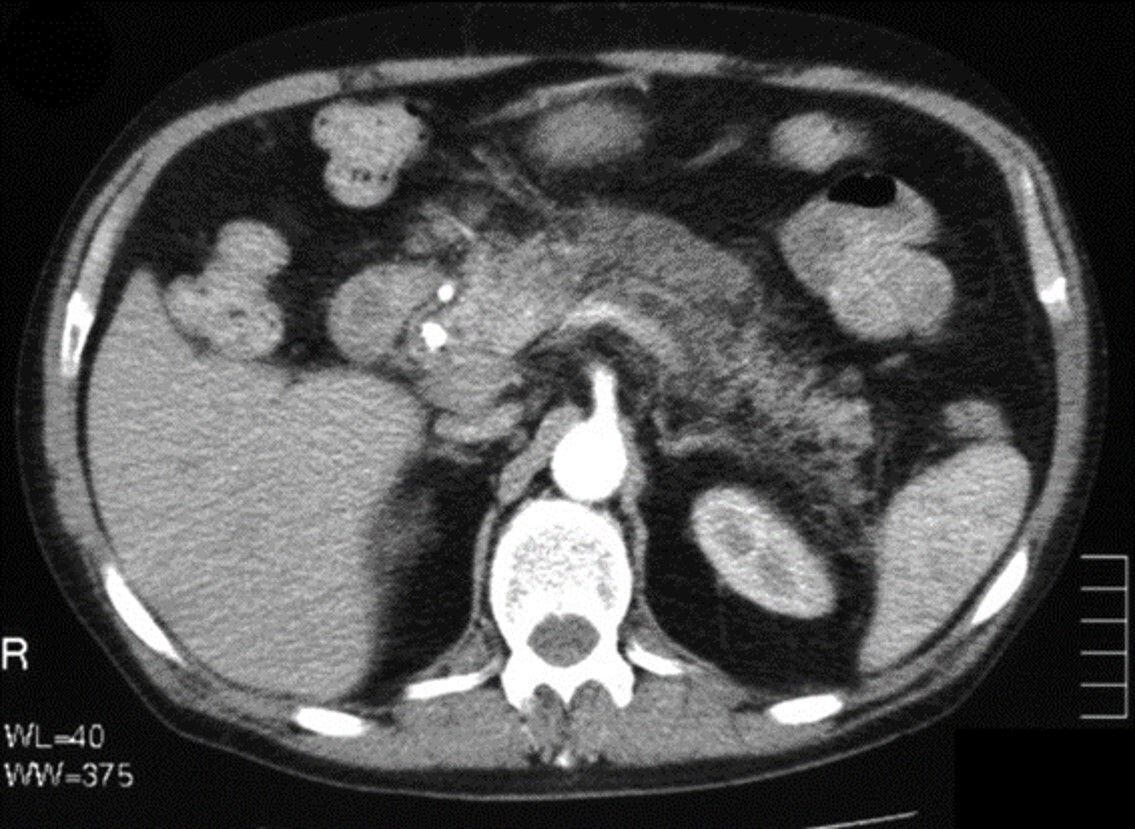

What phase of contrast enhancement is seen in the abdomen CT image?

a Arterial

b. Venous

c. Early Arterial

d. Only inherent contrast is seen in the image

A

Only inherent contrast is seen in the image